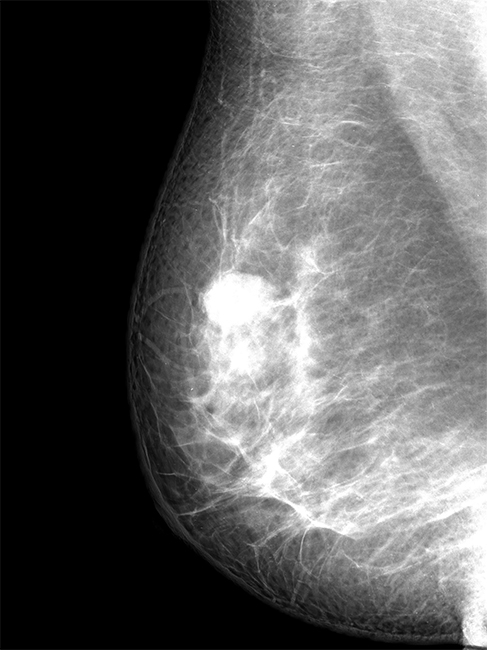

Oana moise medic primar radiologie si imagistica. Aceasta metoda poate evidentia prezenta unor microcalcificari la nivelul sanului putand repera tumorile mamare cu ani de zile inainte de aparitia simptomelor. Daca ai peste 40 de ani nu ai făcut niciodată sau în ultimii doi ani o mamografie ai venitul sub 1600 ron luna vino cu recomandare de la medic sau te ajutăm noi si beneficiezi de mamografie gratuita si interpretare la clinica sala palatului. Mamografia reprezinta o serie de radiografii care prezinta imagini ale tesuturilor moi ale sanului.

Mamografie bilaterala anual completata de ecografie mamara daca este necesar dr. Mamografia este o investigatie care foloseste raze x pentru a evalua sanatatea sanilor si joaca un rol cheie in depistarea precoce a cancerului de san si reducerea numarului de decese provocate de aceasta afectiune. Este o procedura de screening valoroasa care poate detecta cancerul de san intr un stadiu incipient chiar cu doi ani inainte ca un nodul sa poata fi palpat. Este o examinare sigura atunci cand este efectuata de catre radiologi si tehnicieni special pregatiti sa minimizeze expunerea la radiatii este frecvent folosita in cazul fracturilor dar si pentru a examina toracele abdomenul si tesuturile moi superficiale.

Acest lucru reduce mult mortalitatea si pemite prin mijloace terapeutice optime vindecarea bolii dr. Spre deosebire de mamograful analog in care imaginile sunt printate pe film mamograful digital permite radiologului sa capteze si sa manipuleze imaginile astfel incat anomaliile sa fie vizualizate cat mai bine. Totusi controlul regulat cu ajutorul mamografiei este cea mai buna metoda de a descoperi cancerul de san inainte sa apara semne sau simptome evidente. Cancerul mamar reprezinta principala cauza de deces la femeile peste 40 de ani.